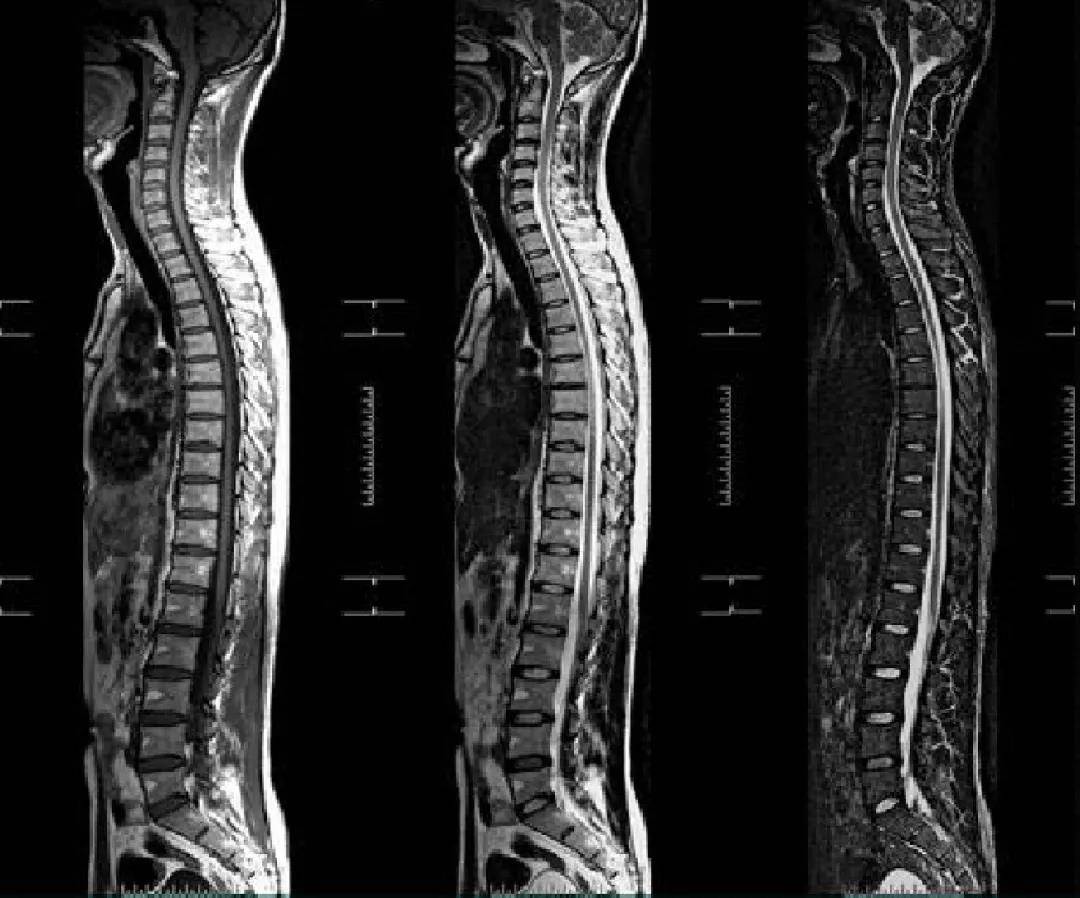

全脊柱MRI

文章图片